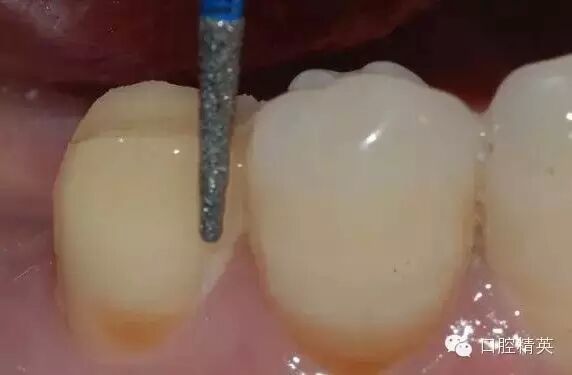

鄰面的制備,先用較細(xì)的金剛砂車(chē)針貼基牙鄰面制備,勿損傷鄰牙